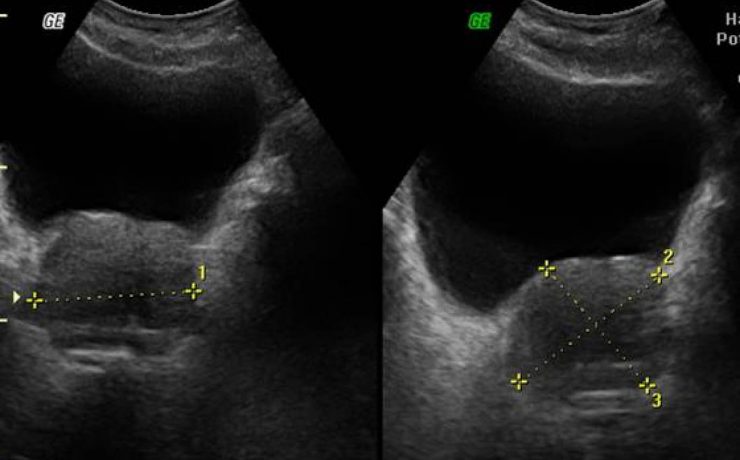

Revista Anales de Radiología de México. Ultrasonido Tiroideo en pacientes dediatricos del HIM, con diagnostico clínico de Tiroiditis de Hashimoto. México 2012 (11) – 1. Se revisaron 64 pacientes, por US más frecuente en mueres 9/1, y la lesión común es nódulo único, hipoecogénico, con contenido sólido, con vascularidad periférica.